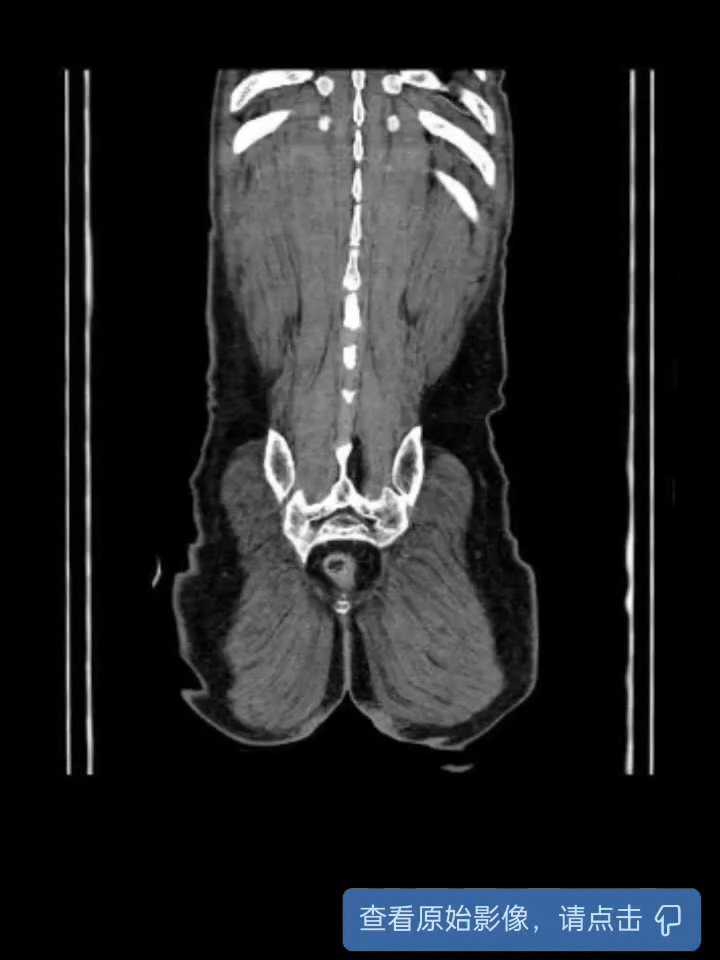

【检查】:下腹部CT平扫:1、扫及回盲部肠壁增厚伴周围渗出、淋巴结肿大,建议完善盆腔CT及进一步检查。2、右肾上腺多发钙化灶。3、腹主动脉及双侧髂动脉硬化。胃镜示:1、十二指肠球部溃疡(S2期)伴狭窄;2、慢性非萎缩性胃炎肠镜示:1、回盲部占位:Ca?;2、内痔。病理检查:“回盲部”低分化腺癌。

【临床诊断】:1、回盲部腺癌2、十二指肠球部溃疡伴狭窄3、慢性非萎缩性胃炎4、食管炎5、内痔。